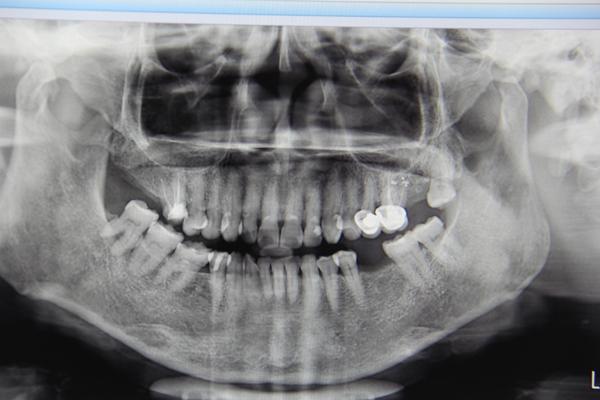

郑阿姨的牙齿拍片情况

今天参与手术直播的是一位67岁的郑阿姨,手术医生冯医生为郑阿姨种植的是左下第6颗牙齿。在手术开始前,专家对郑阿姨的牙齿情况进行了会诊。